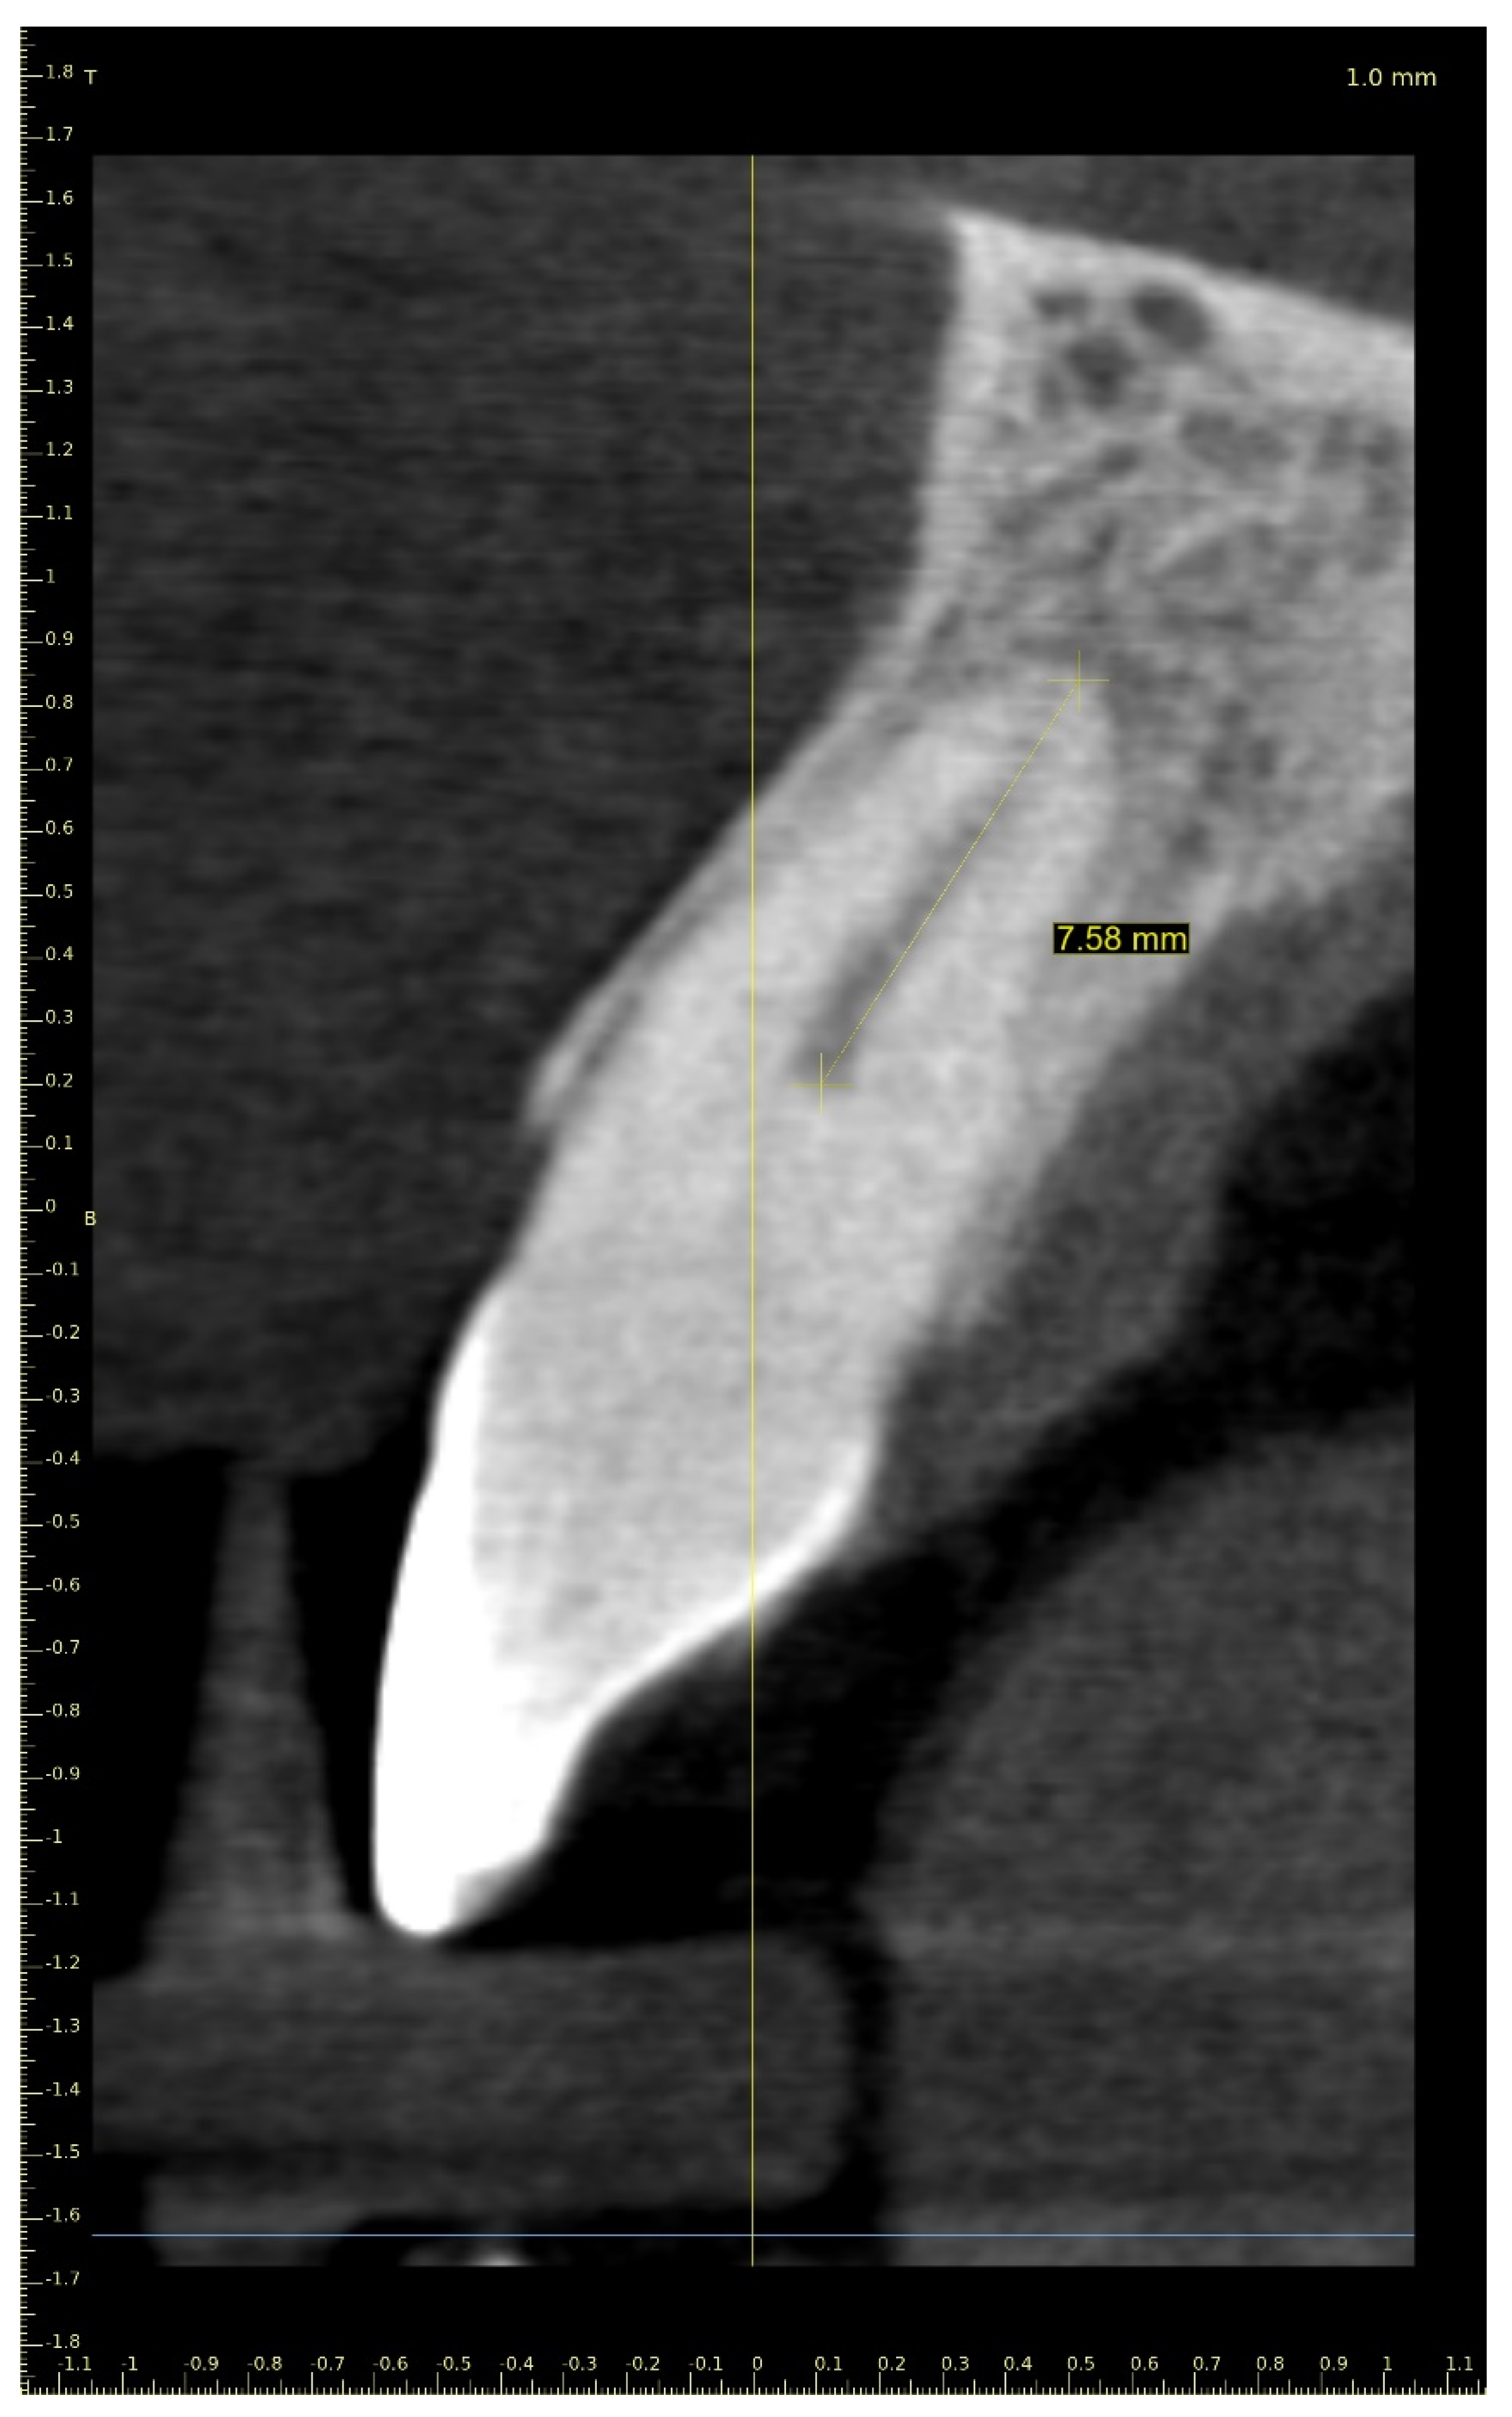

A 21-year-old female patient reported to the endodontic specialist complaining of moderate pain upon percussion of her maxillary central left incisor (tooth 21), experienced for several weeks. The patient was healthy and had no general or chronic diseases. Her dental history revealed that she had experienced dental trauma a few years earlier. The clinical examination revealed a slightly discoloured maxillary left central incisor, tenderness to percussion, a negative response to the pulp sensibility test (cold test), and moderate pain during soft tissue palpation in the apical region of the maxillary central left incisor. Radiographic images revealed the pulp canal calcification and an absence of the canal light that extended to the middle. A CBCT scan was performed (CS 8100 3D, Carestream, 50 × 50 mm) that confirmed canal calcification. The root canal lumen was visible 7.58 mm from the apex (Figure 8). Due to the possible risk of higher tooth substance loss and perforation during endodontic access, we decided to perform the endodontic treatment with guided access.

Figure 8. CBCT sagittal view image revealed a 7.58-mm-long visible part of the root canal on tooth 21 (FDI).